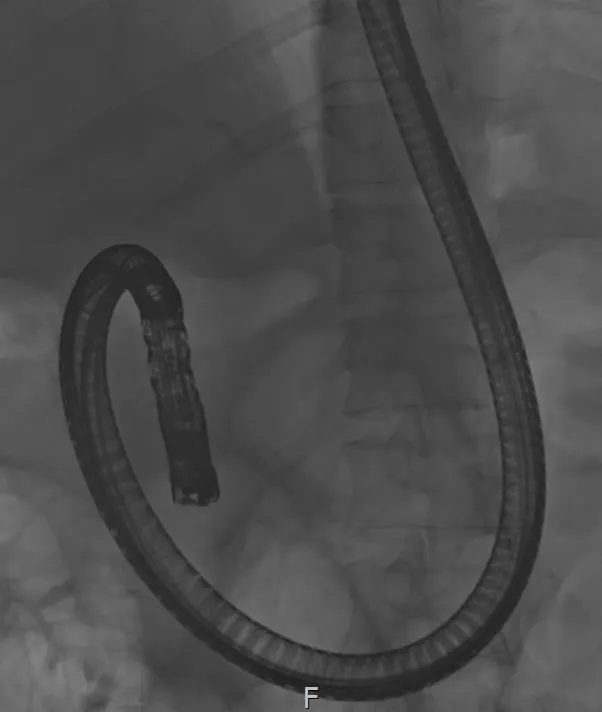

다음 날 ERCP를 시행하였고, 췌장의 괴사로 인해 십이지장 벽이 부어있었고, 십이지장으로의 내시경 통과가 쉽지 않았다. 정상적으로 십이지 장경(ERCP를 위한 내시경을 말한다.) 은 십이지장 2부에서 단축이 가능하나, 이분은 불가능하였다. 단축이 되면 내시경으로 인한 통증이 경감되나, 단축이 되지 않는 경우 내시경이 위 내에서 위를 계속 밀게 되어 시술이 매우 어렵고 환자도 통증을 심하게 호소한다. 진정 내시경(환자들이 흔히 수면 내시경이라고 불리는 말이다.) 이어도 통증은 느낄 수 있다.

정상적으로 내시경이 단축된 모습. 이런 경우는 환자가 통증이 심하지 않아 시술이 용이하다.